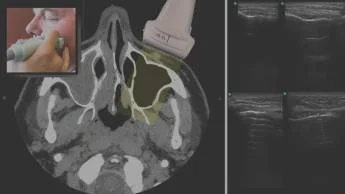

Онлайн-запись на приёмУЗИ пазух носа — это метод визуализации, который помогает врачу оценить состояние воздухоносных полостей лица и определить признаки воспалительных изменений. Метод информативен для обследования гайморовых пазух, визуализация лобных пазух зависит от анатомических особенностей строения лобной кости. Диагностика решетчатого лабиринта и клиновидной пазухи ограничена из-за их расположения и плотности костных структур.

УЗИ пазух носа помогает определять:

- признаки воспалительных изменений, включая утолщение слизистой оболочки, снижение пневматизации и наличие жидкостного содержимого;

- уровень жидкости, ее эхоструктуру и другие ультразвуковые характеристики синусита;

- кисты, крупные полипы и отдельные объемные образования;

- состояние мягких тканей лица и изменения наружных костных контуров.

Пациент располагается сидя. Врач перемещает датчик по области нижних век, щек и лба, оценивая состояние носовых пазух в разных плоскостях.